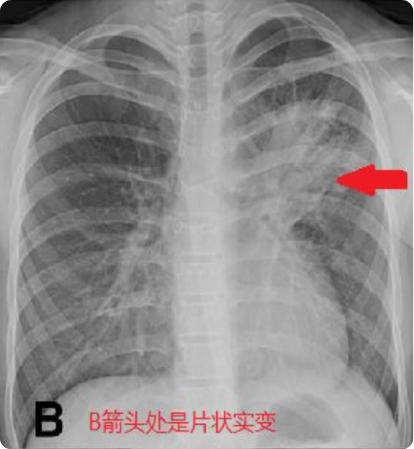

从去年延续至今的儿童肺炎支原体感染一直居高不下,期间再交替出现的流行性感冒病毒、腺病毒等等,各种呼吸道感染病原轮番上阵,不少孩子不幸中招罹患肺炎,而其中出现大片肺实变、肺不张者非常常见,重症肺炎者也不乏少数,甚至有“白肺”的发生,这样的孩子在常规的肺炎治疗基础上,应该如何更好地肺康复呢?

哪些儿童需要接受肺康复?①常见的呼吸系统疾病:大叶性肺炎、肺不张、闭塞性支气管炎、闭塞性细支气管炎、间质性肺疾病、支气管扩张、囊状纤维化、原发性纤毛运动障碍、支气管哮喘等;